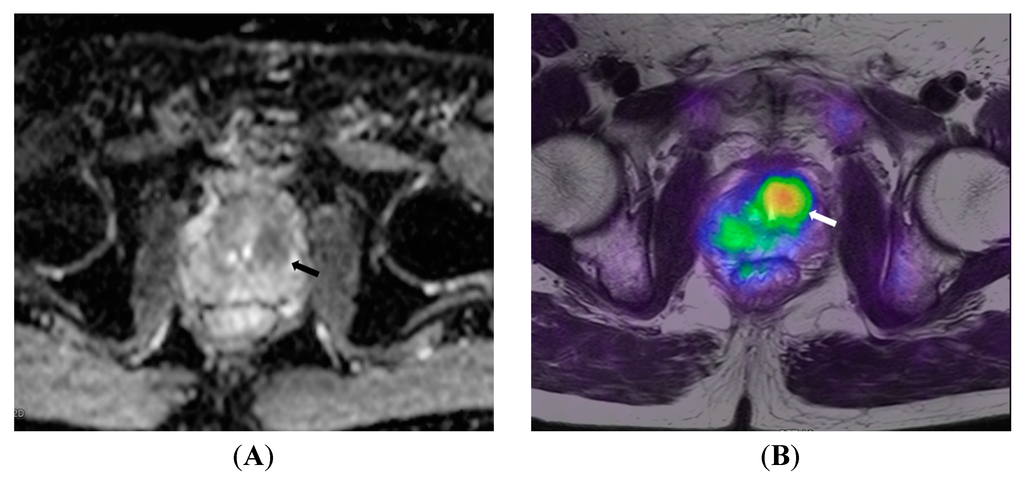

5.3. Genitourinary System Malignancy

- Souvatzoglou, M.; Eiber, M.; Takei, T.; Fürst, S.; Maurer, T.; Gaertner, F.; Geinitz, H.; Drzezga, A.; Ziegler, S.; Nekolla, S.G.; Rummeny, E.J.; Schwaiger, M.; Beer, A.J. Comparison of integrated whole-body [11C]choline PET/MR with PET/CT in patients with prostate cancer. Eur. J. Nucl. Med. Mol. Imaging 2013, 40, 1486–1499. [Google Scholar] [CrossRef] [PubMed]

- De Perrot, T.; Rager, O.; Scheffler, M.; Lord, M.; Pusztaszeri, M.; Iselin, C.; Ratib, O.; Vallee, J.-P. Potential of hybrid 18F-fluorocholine PET/MRI for prostate cancer imaging. Eur. J. Nucl. Med. Mol. Imaging 2014, 41, 1744–1755. [Google Scholar] [CrossRef] [PubMed]

- Kim, Y.; Cheon, G.J.; Paeng, J.C.; Cho, J.Y.; Kwak, C.; Kang, K.W.; Chung, J.-K.; Kim, E.E.; Lee, D.S. Usefulness of MRI-assisted metabolic volumetric parameters provided by simultaneous 18F-fluorocholine PET/MRI for primary prostate cancer characterization. Eur. J. Nucl. Med. Mol. Imaging 2015, 42, 1247–1256. [Google Scholar] [CrossRef] [PubMed]

- Wetter, A.; Lipponer, C.; Nensa, F.; Beiderwellen, K.; Olbricht, T.; Rubben, H.; Bockisch, A.; Schlosser, T.; Heusner, T.A. M.; Lauenstein, T.C. Simultaneous 18F Choline Positron Emission Tomography/Magnetic Resonance Imaging of the Prostate: Initial Results. Invest. Radiol. 2013, 48, 256–262. [Google Scholar] [CrossRef] [PubMed]

- Park, H.; Wood, D.; Hussain, H.; Meyer, C.R.; Shah, R.B.; Johnson, T.D.; Chenevert, T.; Piert, M. Introducing Parametric Fusion PET/MRI of Primary Prostate Cancer. J. Nucl. Med. 2012, 53, 546–551. [Google Scholar] [CrossRef] [PubMed]